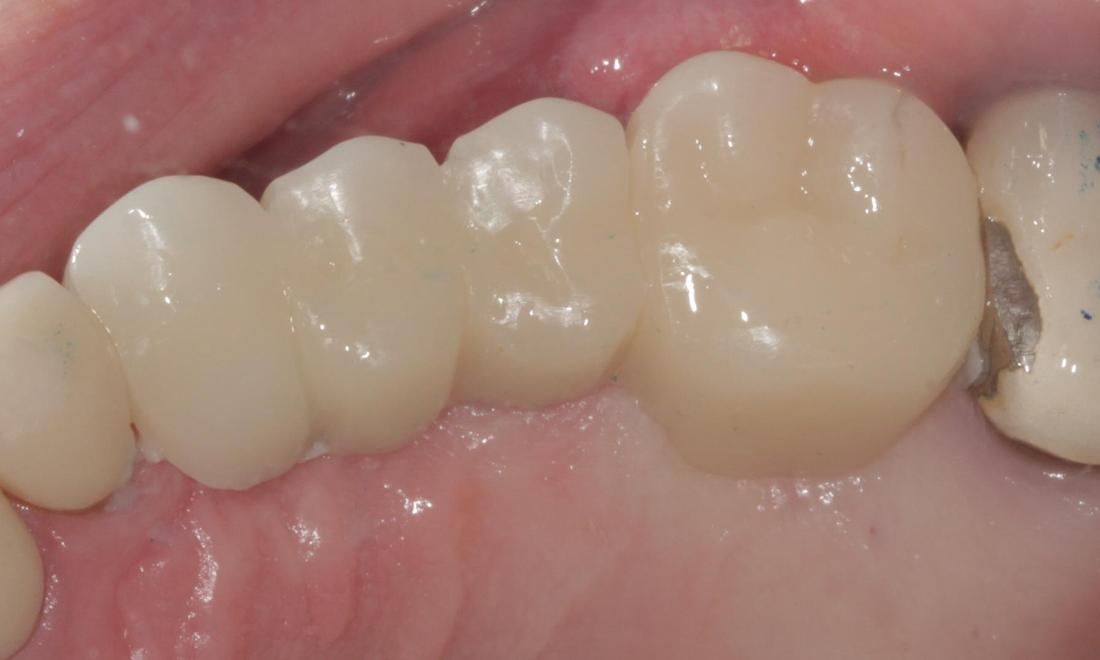

Mini Implant Bridge

This patient had been wearing a removable partial denture for years and was not happy with it. He complained of it moving while he chewed, and said he could not eat many of the foods that he enjoyed. After careful planning, 5 mini dental implants were placed, and a custom bridge was cemented into place. He is now able to chew food again on that side, and he does not have to worry about removing his teeth at night before bed. He called the day after the implants were placed to let us know he was on his way out to go fishing!